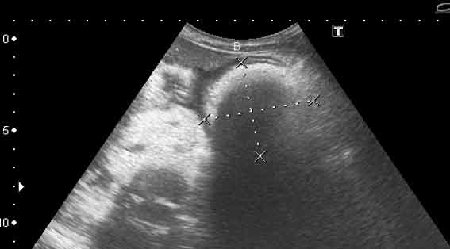

УЗИ, трихобезоар желудка. Gastric trichobesoar, ultrasonography.

Наблюдение наших коллег, работающих в педиатрии (valeriy.andilevko).

УЗИ, девочка 8 лет с ментальными расстройствами.